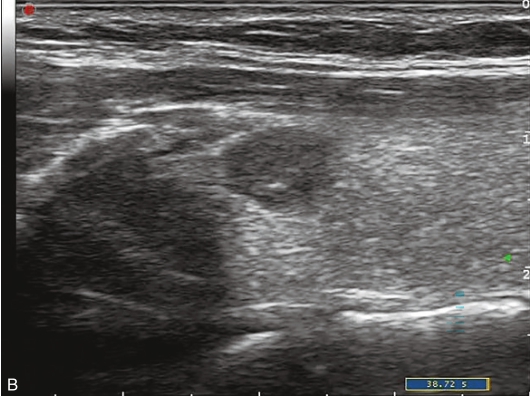

甲状腺右叶中部可见一个肿块,大小约为2.6cm×1.8cm×1.8cm,形状尚规则,边界尚清楚,内部为低回声,分布不均匀,后方回声无变化,CDFI显示肿块内可见丰富的血流信号,见图1-9-1。

图1-9-1 甲状腺髓样癌常规超声图像

A.甲状腺右叶低回声结节纵切面灰阶超声图像;B.甲状腺右叶低回声结节横切面灰阶超声图像;C.CDFI图像